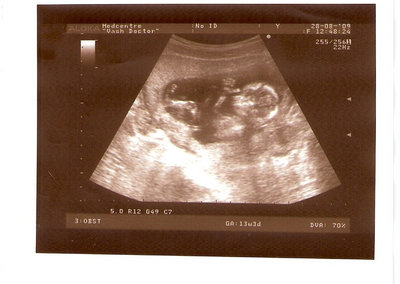

СЫН

| Вложения: |

2.jpg [ 110.14 КБ | Просмотров: 2811 ]

Nikisa писал(а): Foto prosto chudesnoe. A na kakom sroke uznali, chto sin.............. НА 13 НЕДЕЛЯХ.КАК РАЗ ВОТ В ЭТО узи, ОНО УМЕНЯ ВТОРОЕ БЫЛО. ЭТО КОНЕЧНО МАЛЕНЬКИЙ СРОК ДЛЯ ОПРЕДЕЛЕНИЯ ПОЛА. НО Я ПОПРОСИЛА ВРАЧА(ЭТО КТСТАТИВ РОССИИ БЫЛО) ХОТЯ БЫ ПРЕДПОЛОЖИТЬ. ЕЙ ВСЁ ТАКИ УДАЛОСЬ РАССМОТРЕТЬ.НУ ВООБЩЕМ ЧЕРЕЗ НЕСКОЛЬ ДНЕЙ ПОЙДУ К ВРАЧУ, УЖЕ АМЕРЕКАНСКОМУ И УЗНАЮ ТОЧНО. К ТОМУ ВРЕМЕНИ У МЕНЯ БУДЕТ СРОК 18 НЕДЕЛЬ. ХОТЕЛОСЬ БЫ ПОСМОТРЕТЬ НА ДРУГИЕ ФОТО НА ЭТОМ СРОКЕ ИЛИ БОЛЬШЕ. ТАК ЧТО ВЫКЛАДЫВАЙТЕ, ЕСЛИ НЕ ЖАЛКО!